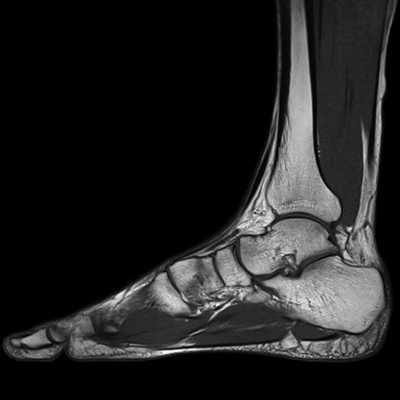

МРТ голеностопного сустава в корональной плоскости.

Отмечается поперечный стресс-перелом дистальных отделов малоберцовой кости.